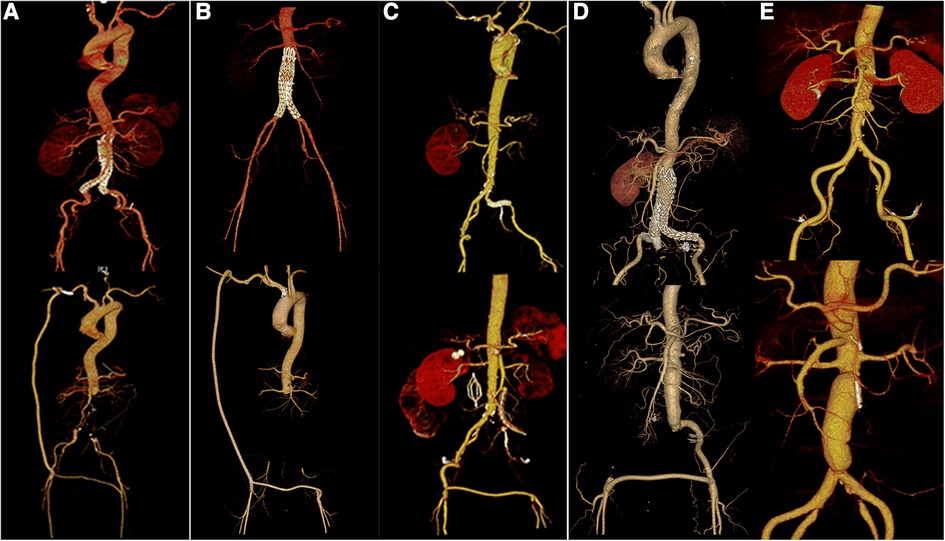

Immediate technical success was achieved intraoperatively in all patients (Figure 5A–E). The mean procedure time was 505 min (range, 370–655 min). All patients underwent autologous whole-blood resuscitation. All patients were transferred to the ICU for further treatment after surgery because of extensive trauma, the long surgical duration and excessive intraoperative bleeding. In these patients, the infecting microorganisms detected by ascites assay included Proteus Mirmiris, Klebsiella pneumoniae, and Staphylococcus epidermidis. Acinetobacter baumannii, Staphylococcus epidermidis, Staphylococcus haemolyticus, Candida albicans, and Morganella were found in blood cultures. All patients received anti-infective therapy with sensitive antibiotics.

Figure 5

(A–E). Preoperative and postoperative CTA data of patients 1–3, 5, and 6, respectively.